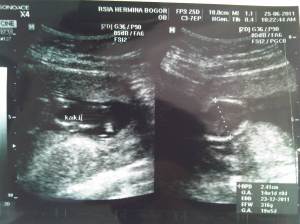

Masuk 14 minggu, detak jantung bagus, kaki sidah kelihatan dan lingkar kepala sudah mulai